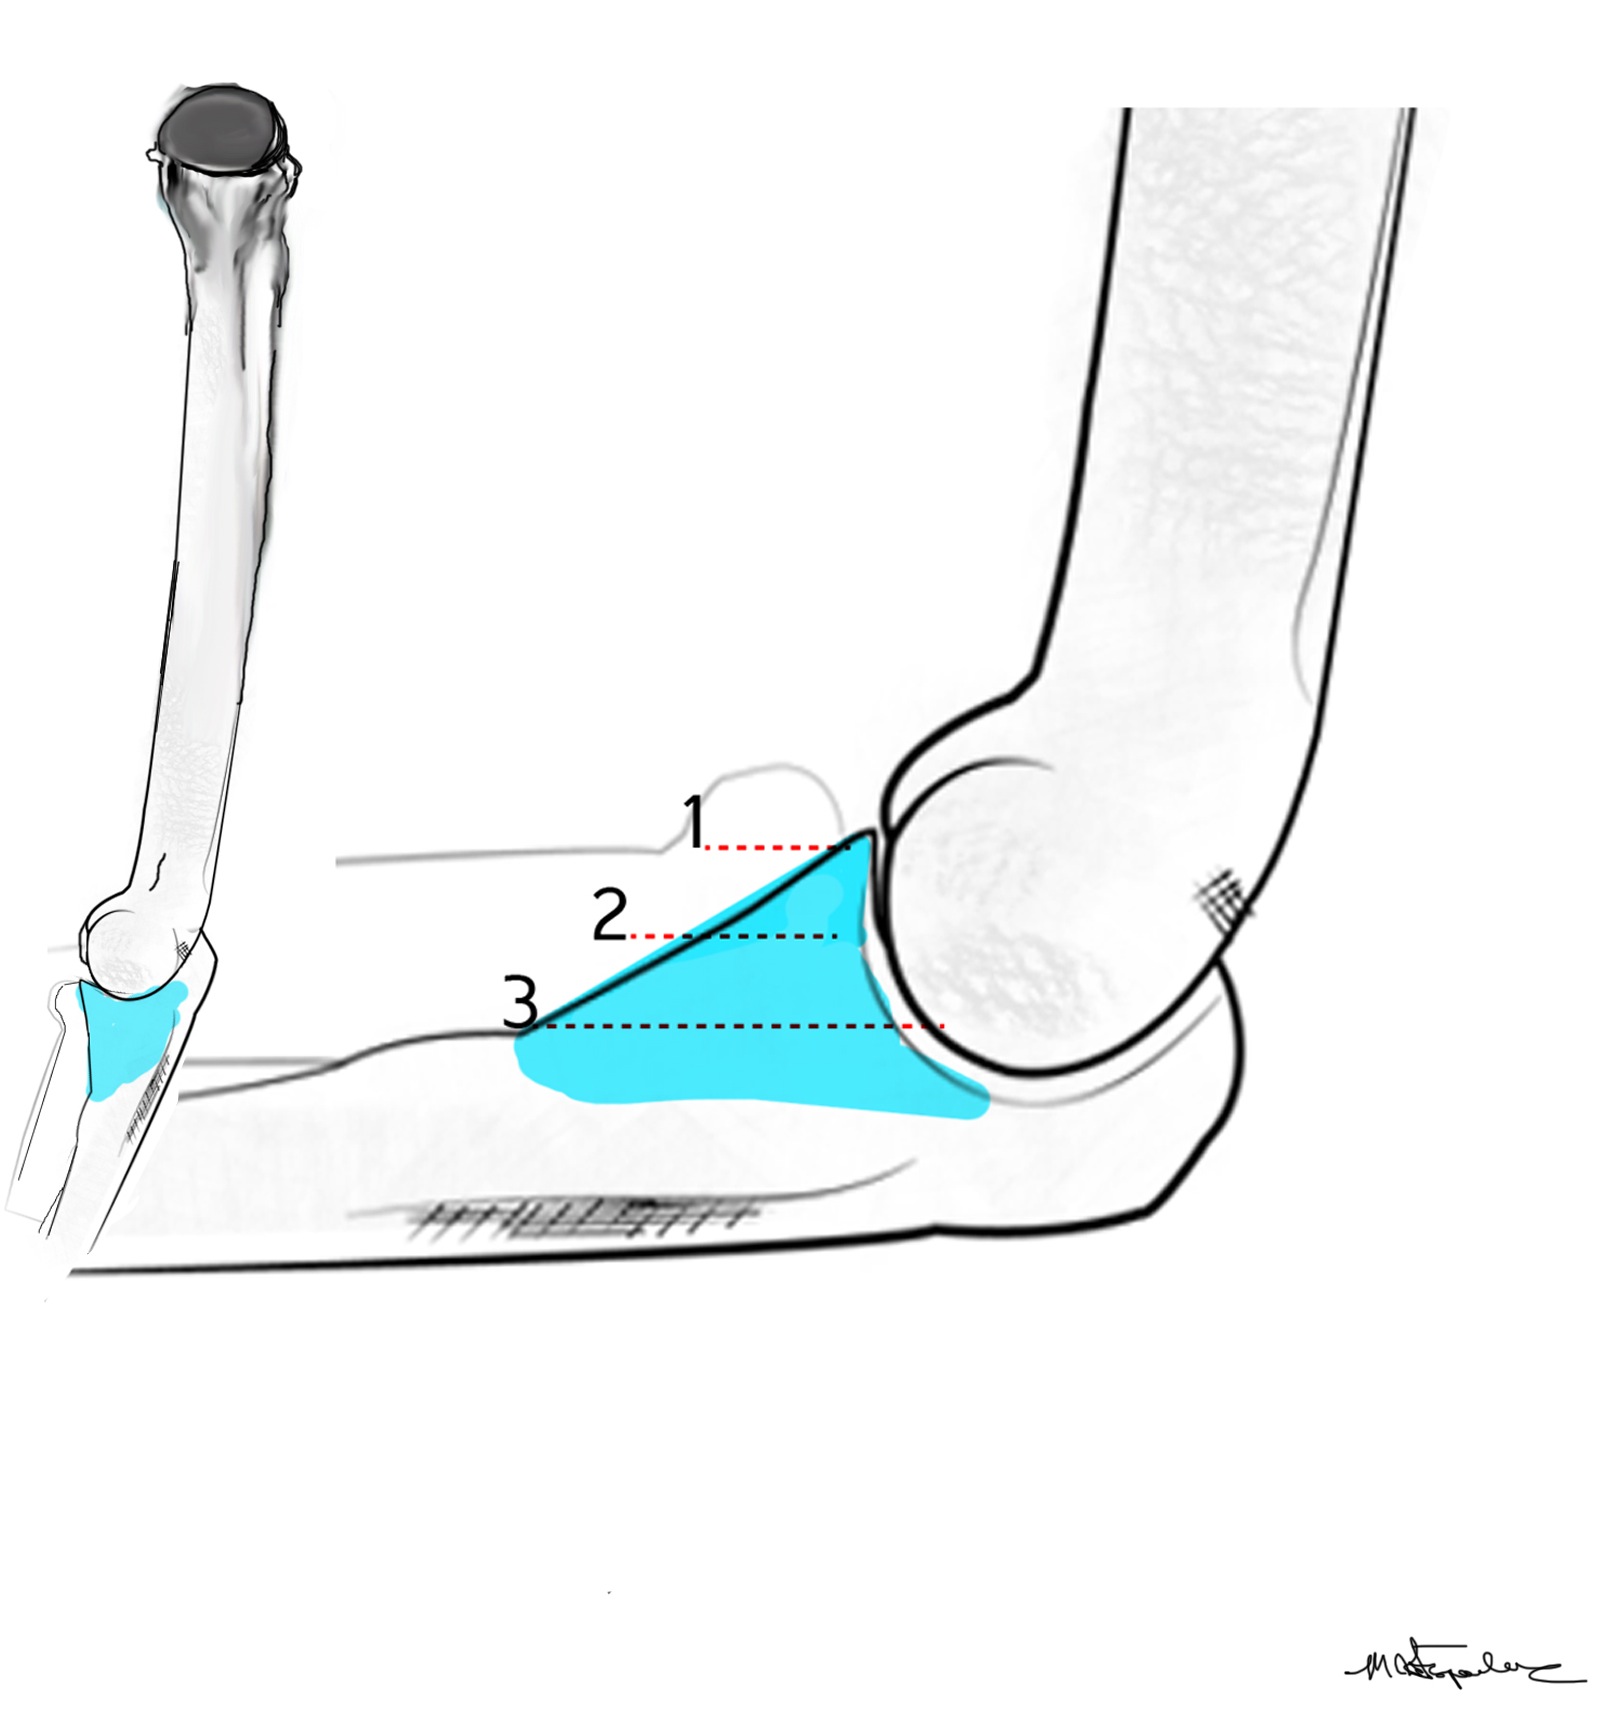

Coronoid process

Coronoid is the most important portion of ulno-humeral articulation

- provides anterior buttress

- attachment of capsule and brachialis

- anterior band of the MCL attaches to it

Regan and Morrey classification of transverse coronoid fractures

Elbow stability related to size of coronoid fragment

O'Driscoll classification anteromedial coronoid facet fractures

Anteromedial coronoid facet fragment

- associated with varus posteromedial rotational force

- associated with tear of lateral ulna collateral ligament (LUCL)